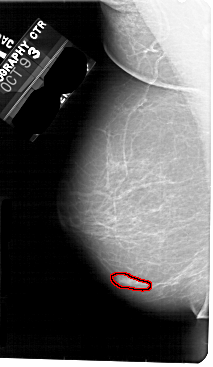

A_1793_1.LEFT_CC

FILE: A_1793_1.LEFT_CC.OVERLAY

TOTAL_ABNORMALITIES 1

ABNORMALITY 1

LESION_TYPE MASS SHAPE LOBULATED MARGINS OBSCURED

ASSESSMENT 4

SUBTLETY 4

PATHOLOGY BENIGN

TOTAL_OUTLINES 1

BOUNDARY